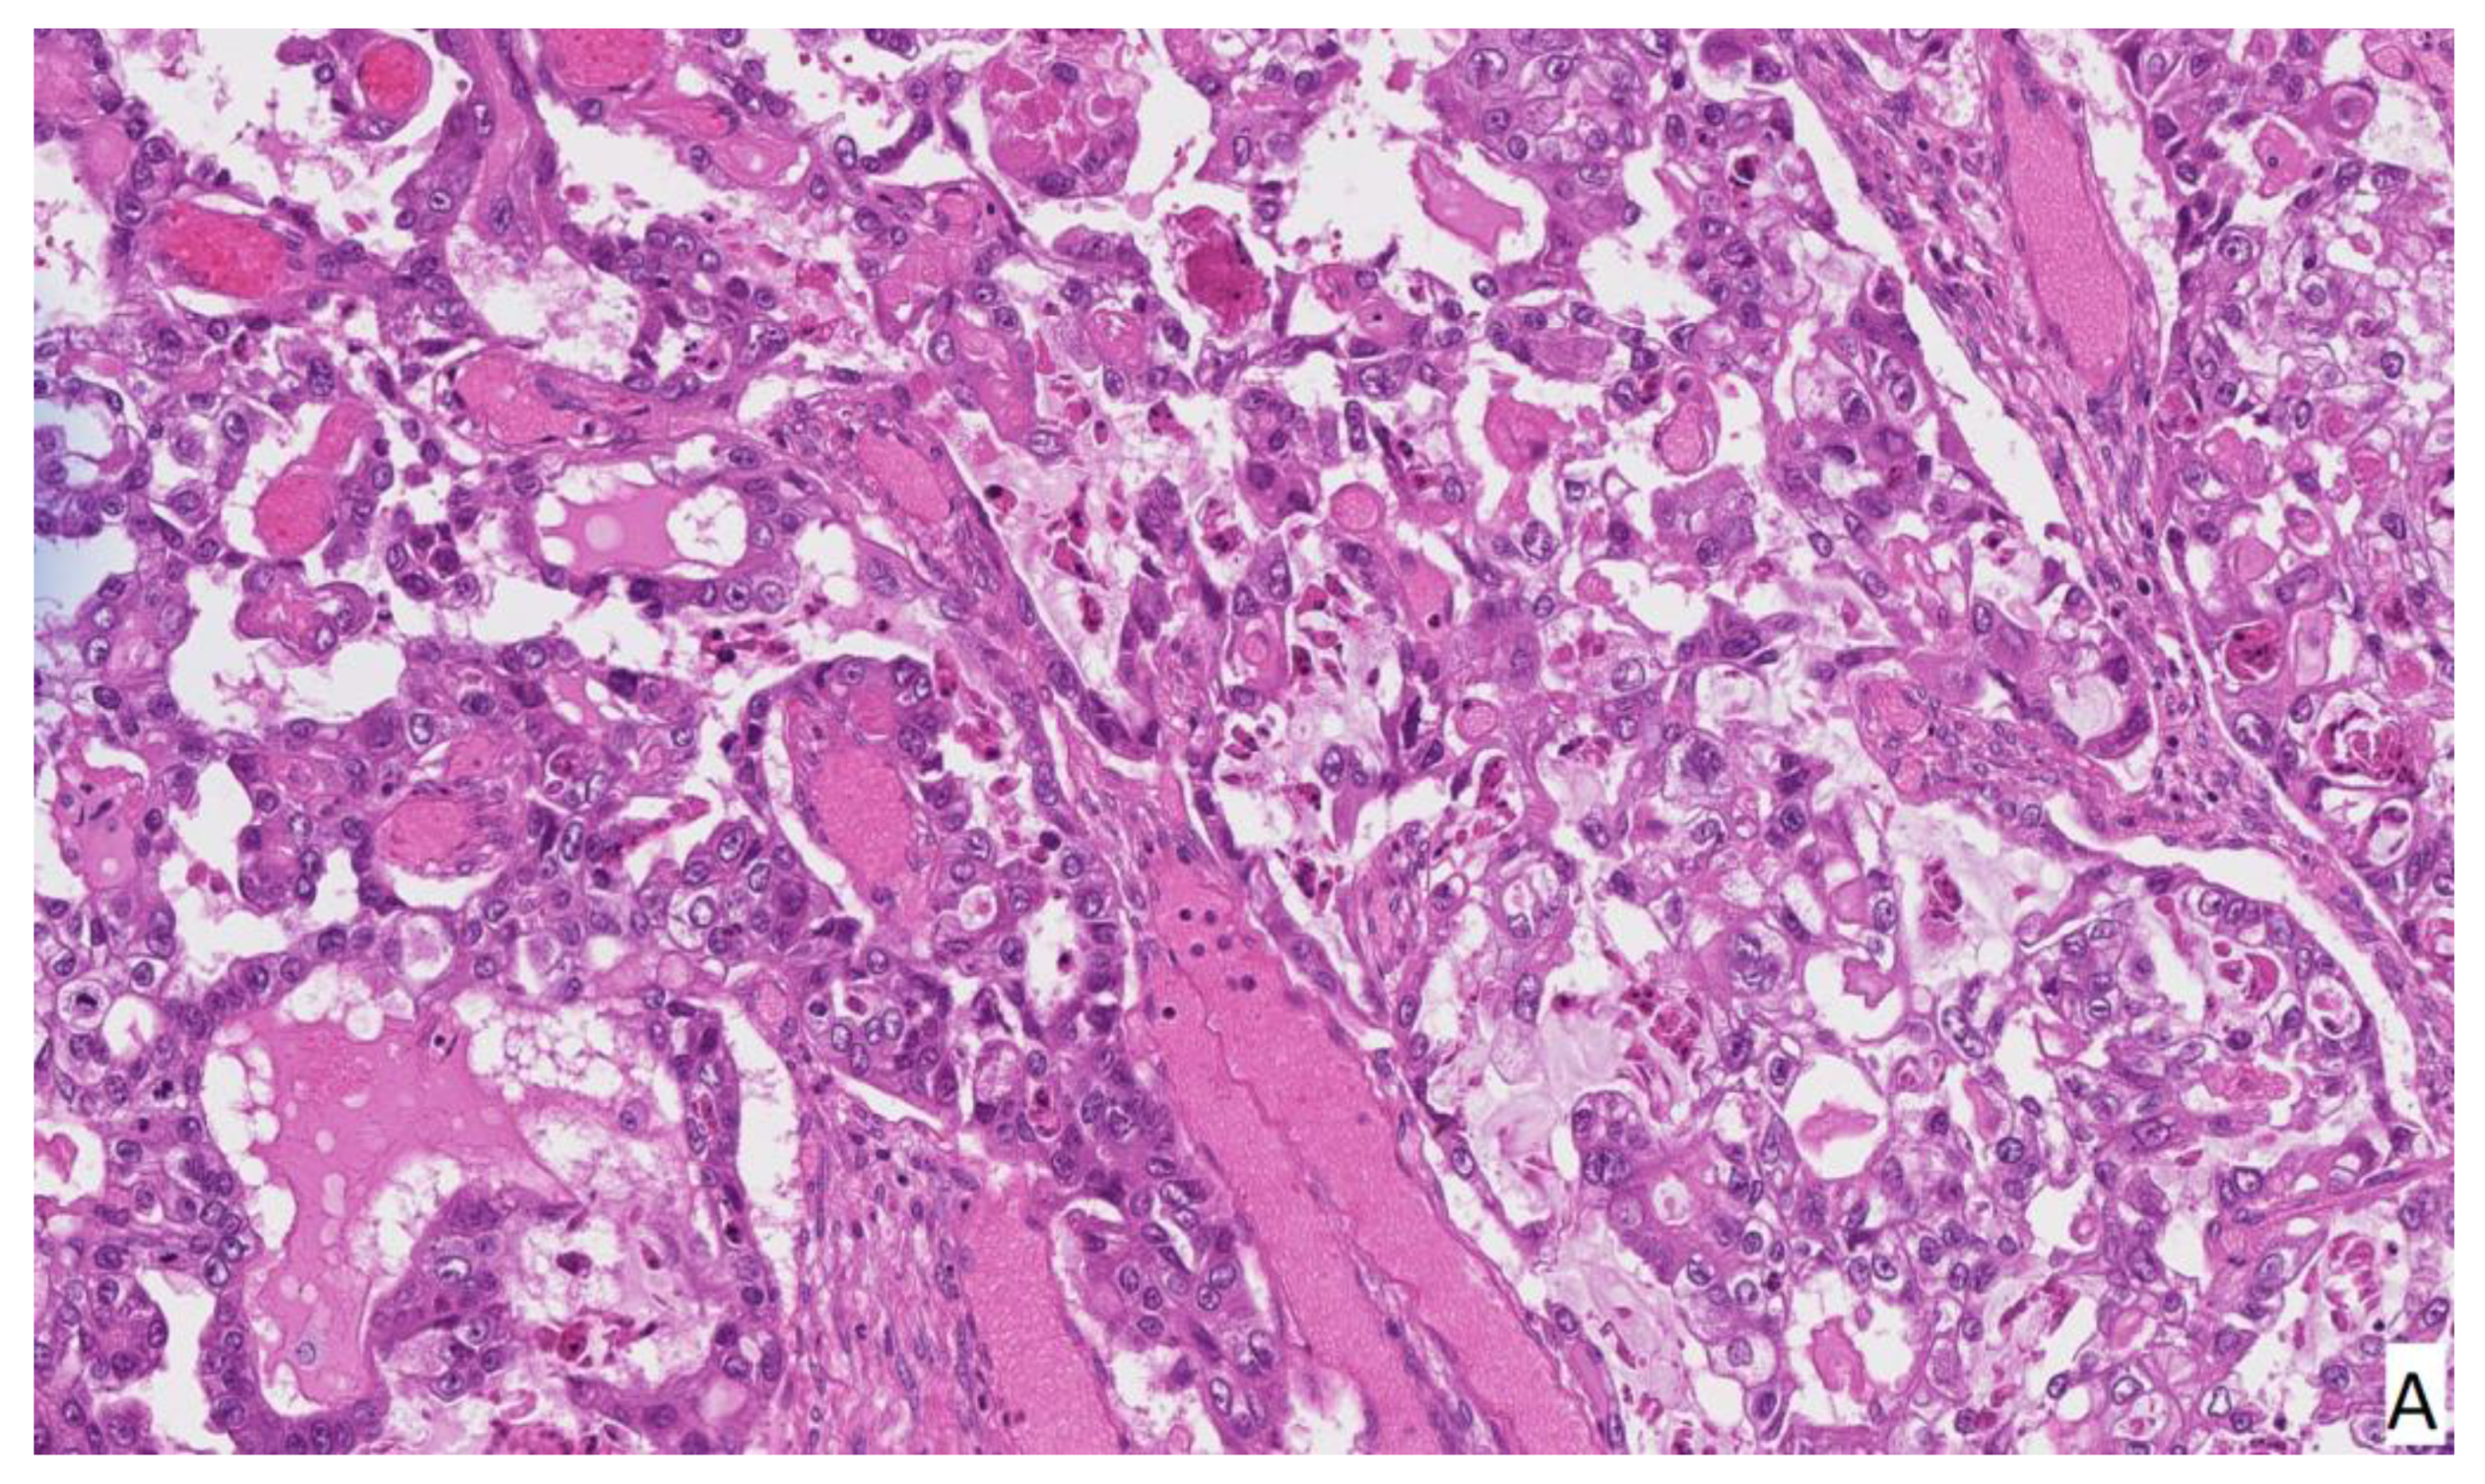

2. Case Report